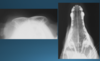

What is shown in these images?

Top Left and Right:

-hydrocephalus with doming of cranial vault

Bottom Left:

-normal